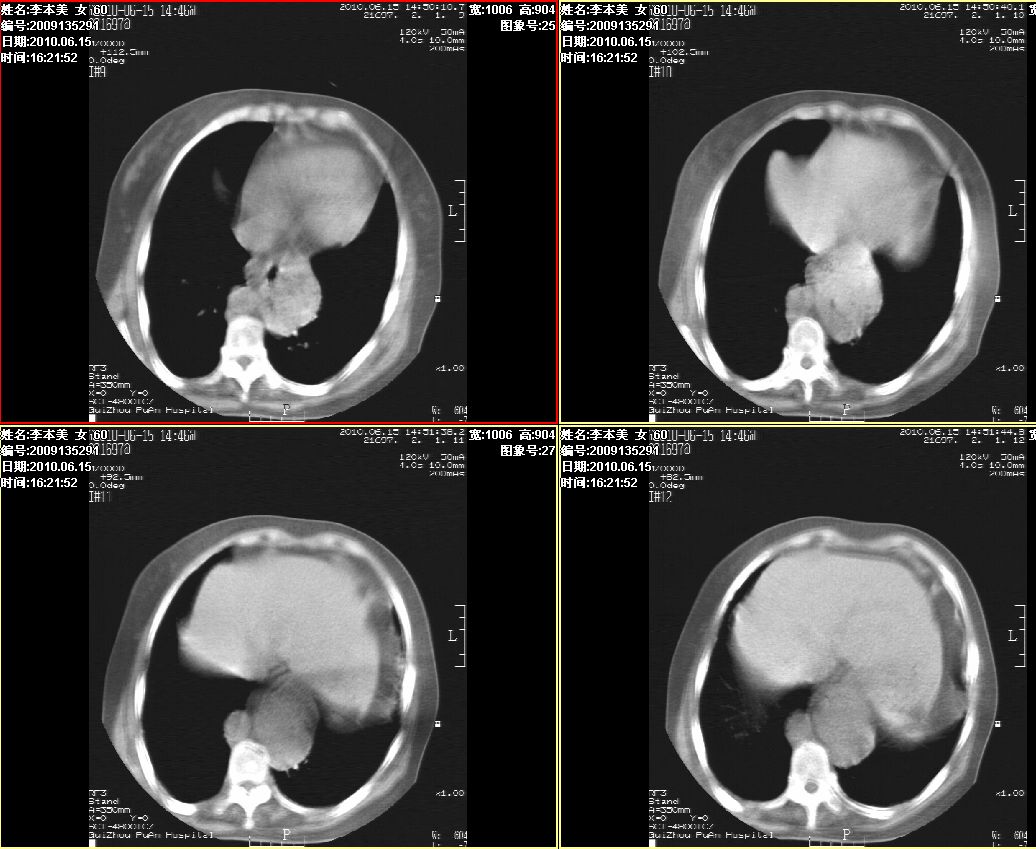

李某,60岁,女,胸闷气促一月,照片发现心后缘圆形高密度影,ct扫描如下。请大家看看,描述一下,给个诊断意见。

降主动脉夹层动脉瘤,建议增扫

占位或夹层动脉瘤,增强扫描

图像欠清,主动脉瘤?食管肿瘤?食管裂孔疝?建议增强。

考虑为:食管裂孔疝; 不排除食道下段肿瘤性病变。

考虑为:食管裂孔疝; 不排除食道下段肿瘤性病变

支持夹层动脉瘤,建议cta。

食管裂孔疝; 不排除食道下段肿瘤性病变。

考虑食管裂孔疝, 食管下段肿瘤性病变待排;建议行进一步检查。

主动脉瘤?食管肿瘤?食管裂孔疝?建议增强。

食管癌?